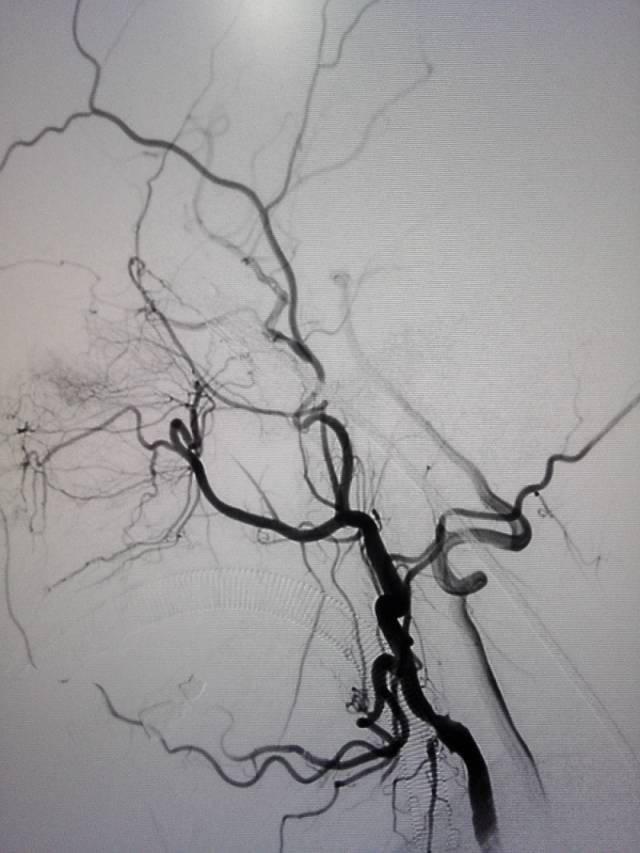

术前三个月造影:右侧颈内动脉几乎不显影。

手术过程:全麻后造影示颈内动脉闭塞,经眼动脉从颅外代偿,经前交通动脉自左侧代偿。

经动脉鞘造影,可见远端颈内动脉淡淡显影。

然后球囊扩张,植入支架。植入支架后造影示右侧颈内动脉开通。